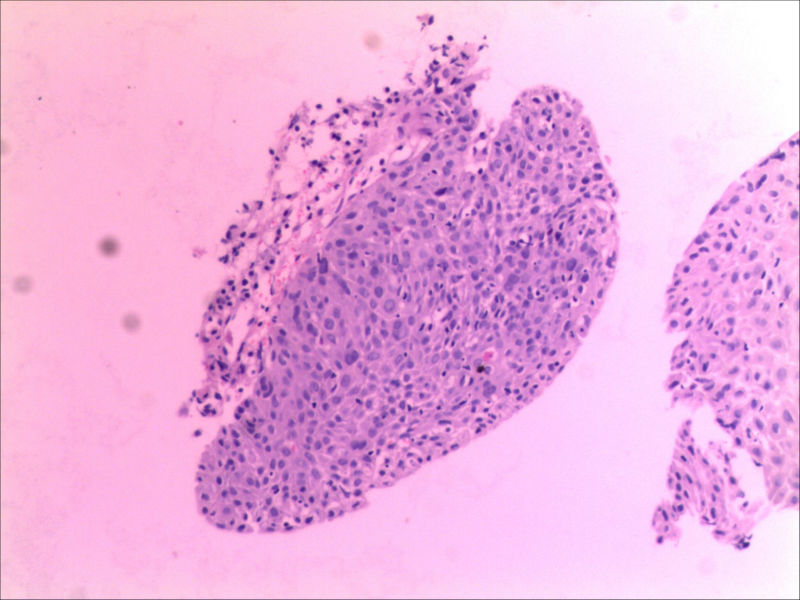

食管活检男64岁食管粗糙

• 食管活检男64岁食管粗糙图2

图2

高级别上皮内瘤变,取材表浅,不排除高分化鳞癌,请结合临床建议必要时再取活检

同意,本例仅出现食管黏膜粗糙,如果没有较大肿块或溃疡,也有可能就是个高度上皮内瘤变或早期食管癌。因此可做超声内镜,如果可能,做大黏膜切除治疗。